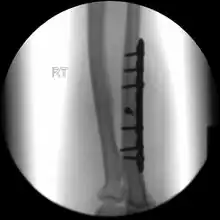

If the fracture is not significantly displaced, is stable, and is not associated with another fracture, it may be treated with a cast for around five to six weeks.[3] This includes fractures that are less than 50% displaced and less than 10 degrees angulated.[6]

During the recovery period healing can be followed up with x-rays.[3] Heavy lifting should be avoided.[3] After the cast has been removed exercises are encouraged and full strength is regained over time.[3] Treatment may may also be with splinting and early movement.[2]

When there is a displaced fracture or when the radioulnar joints are involved an operation is often performed, using either flexible rods or screws and plates in order to reduce the fracture and immobilise the bone.[3]